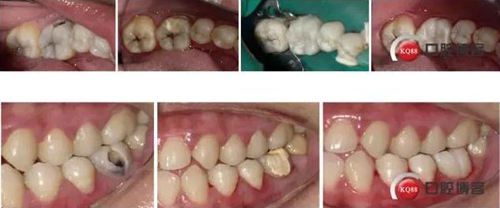

左下6根管治療后樹脂充填 科貿(mào)嘉友收錄

36頰側齲壞發(fā)黑,探診(+),叩診(-),冷刺激(++),松動(-),齦(-)

X-rays示36頰側齲壞達髓角,根尖周無明顯病變

診斷:346慢性牙髓炎

治療計劃:RCT后擇期修復

治療:解釋病情,簽訂治療知情同意書,繳費,斯康杜尼+利多卡因局麻下上橡皮障,去腐,開髓,拔髓,10#K銼疏通根管,10#K銼測根長,MB:21mm;ML:21mm;DB:20.5mm;DL:21mm;NSK機擴馬達,21mmPLEX-V銼,扭力:3.5N.cm,轉(zhuǎn)速:400RPM。P0+EDTA敞開根管口(根管中上1/3),5.25%次氯酸鈉+生理鹽水交替沖洗,干燥,P1+EDTA疏通根管至根管全長,V1、V2+EDTA根管成型,DB,DL根尖1/3融合,5.25%次氯酸鈉沖洗后將次氯酸鈉存于根管內(nèi),蕩洗機關水蕩洗20S/根管,蒸餾水蕩洗20S/根管,干燥,隔濕,AHplus糊劑+2506牙膠尖次氯酸鈉消毒后酒精棉球拭干后垂直加壓充填,置小棉球,暫封膏+聚羧酸鋅水門汀暫封。去除橡皮障,拍片。

處理:去除暫封物,上橡皮障,HE面去腐,備洞,富士2墊底,酸蝕,干燥,涂布粘結劑,光照,流體樹脂襯洞,美塑樹脂充填,下橡皮障,調(diào)合,打磨,拋光

1、對于頰側齲壞的后牙,有事可以就齲開髓,沒必要直接he面開髓,這樣可以保留更多的牙體組織